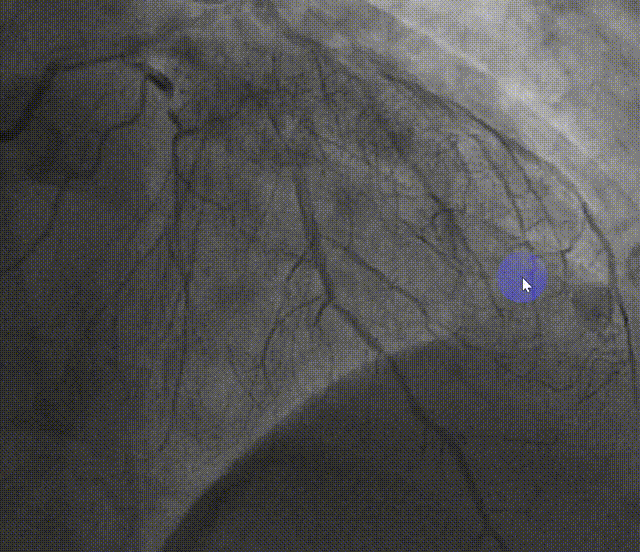

右头位造影提示LM、LAD重度狭窄伴钙化

足位造影LM、LAD重度狭窄

蜘蛛位造影提示LM、LAD重度狭窄伴钙化